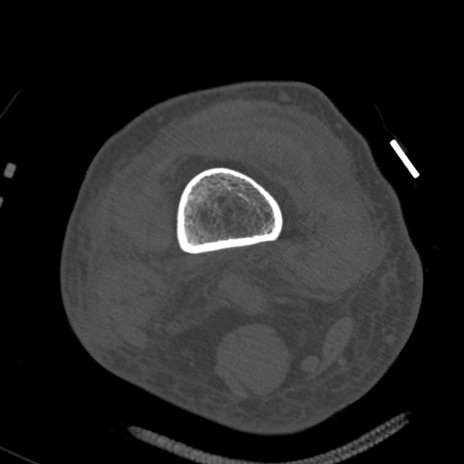

症例28 右膝関節CT(横断像)

右膝関節CT